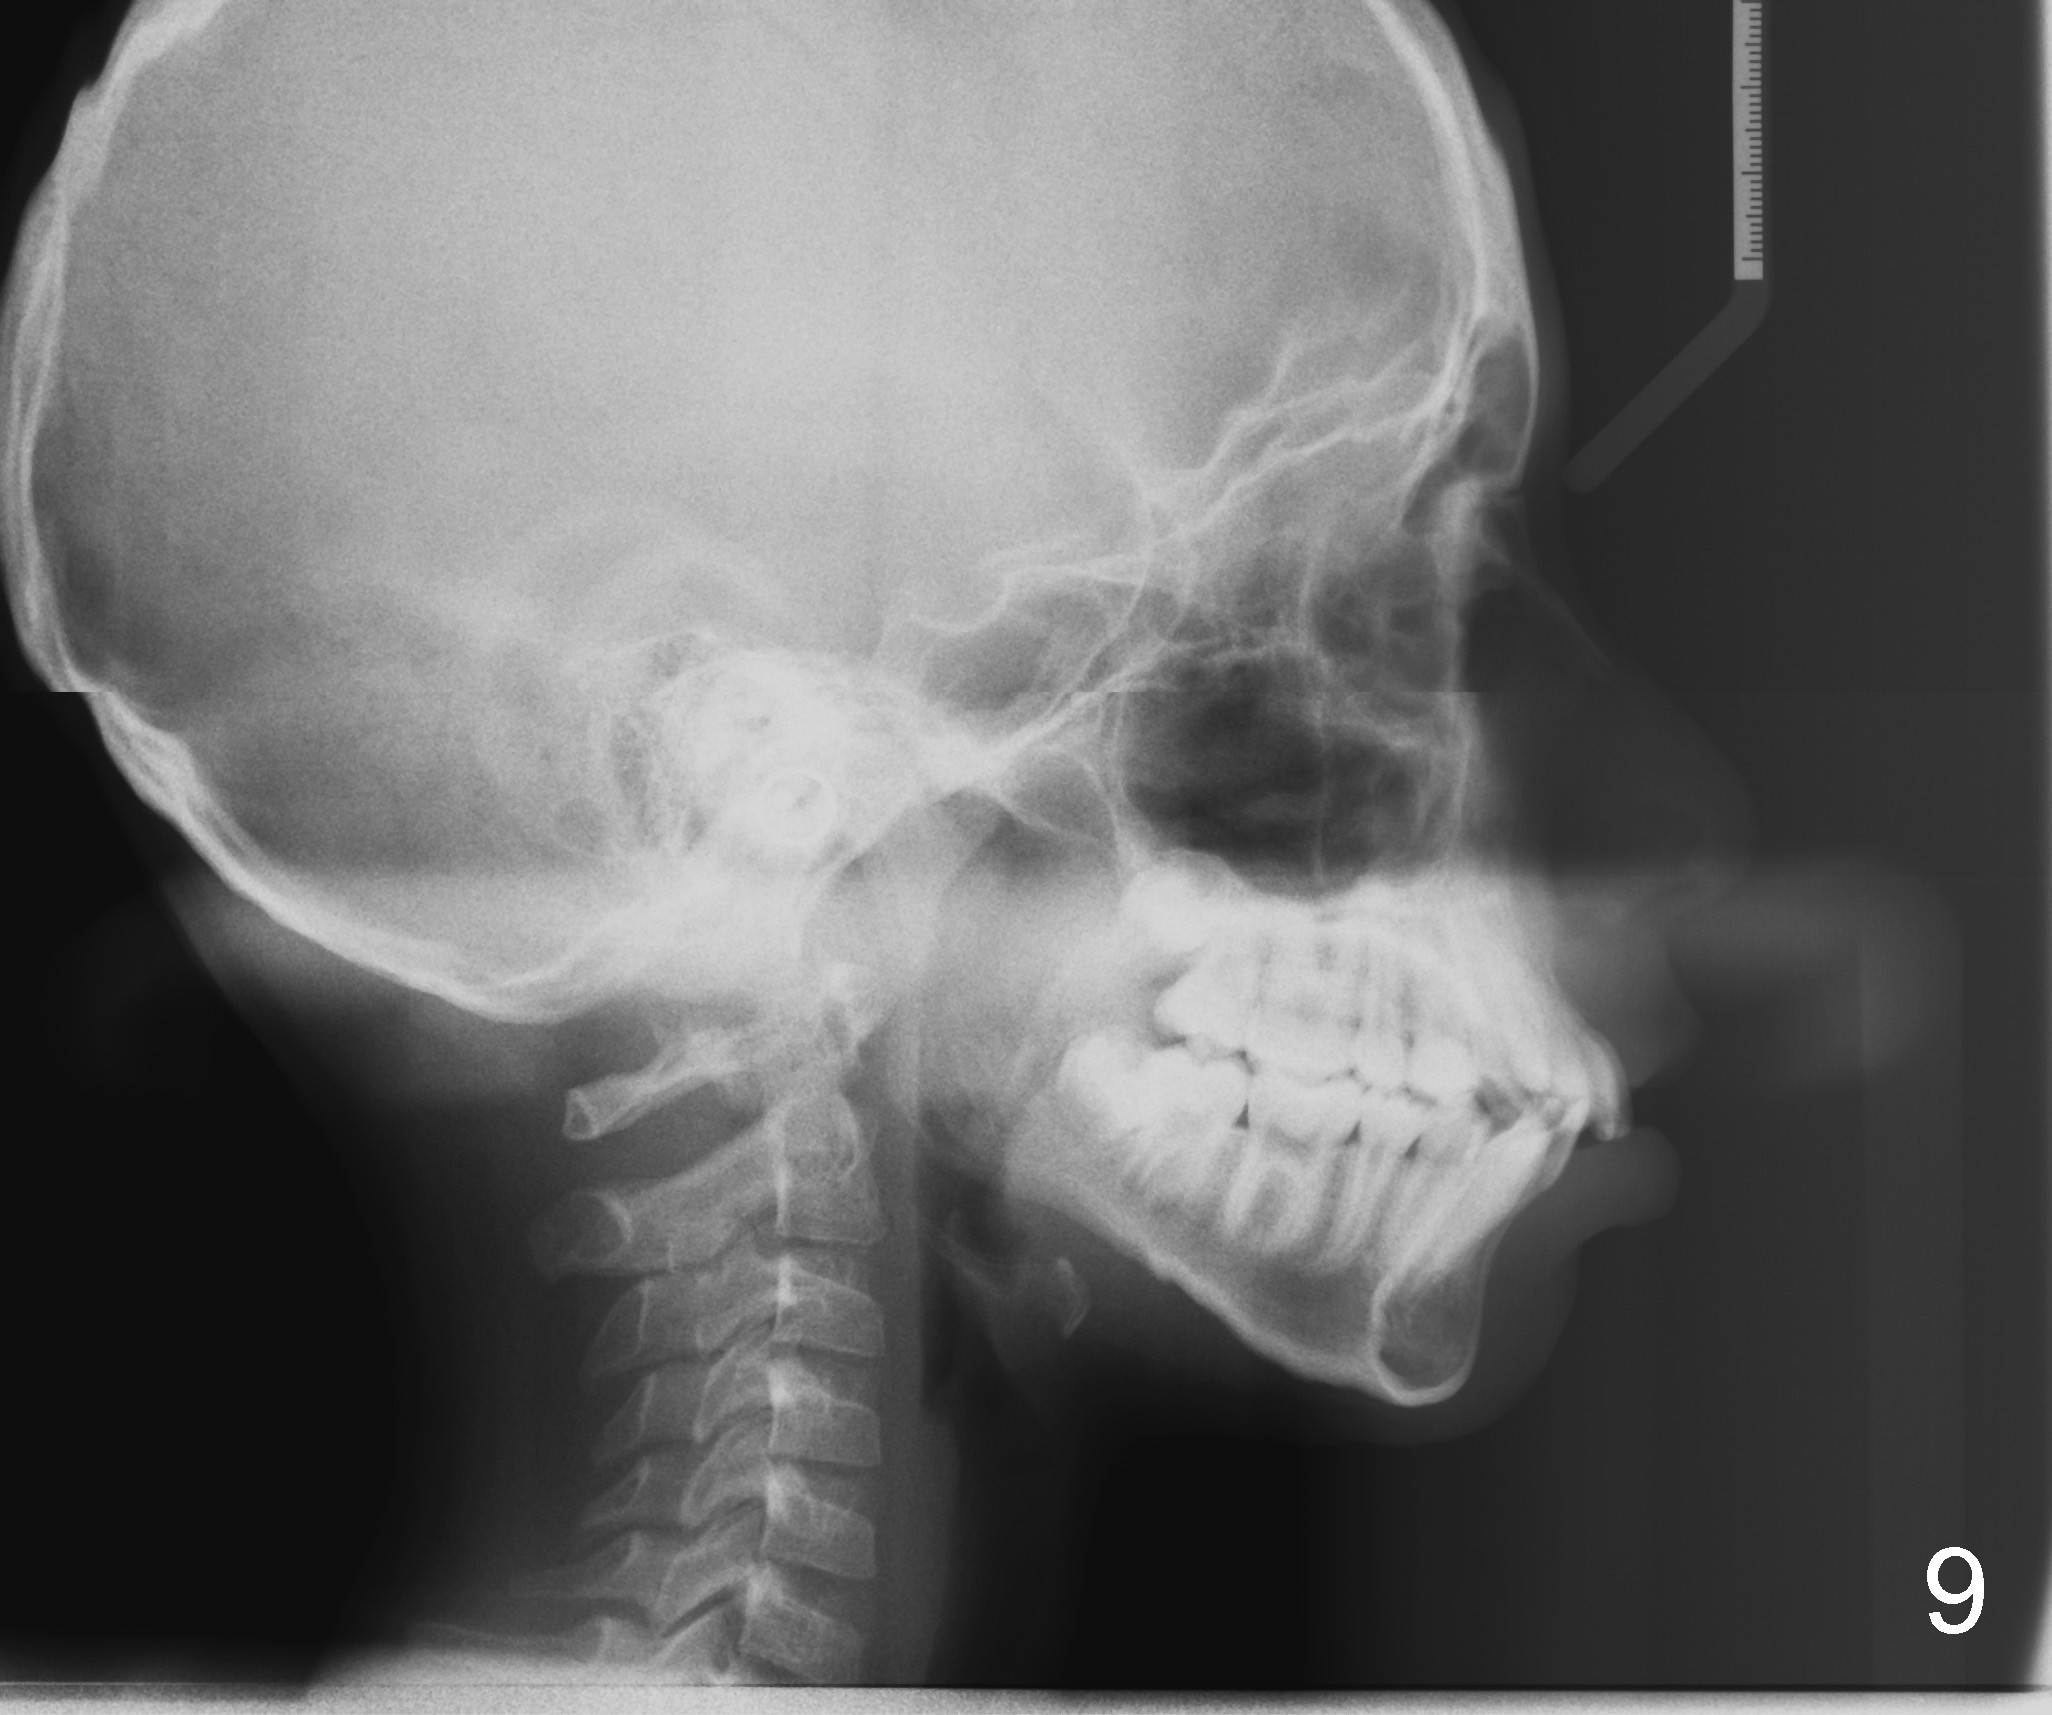

Photos were taken on May 29, 2012 (Fig.1-8), ceph and pan May 24, 2012 (Fig.9,10), post-extraction ceph July 30, 2012 (Fig.11).